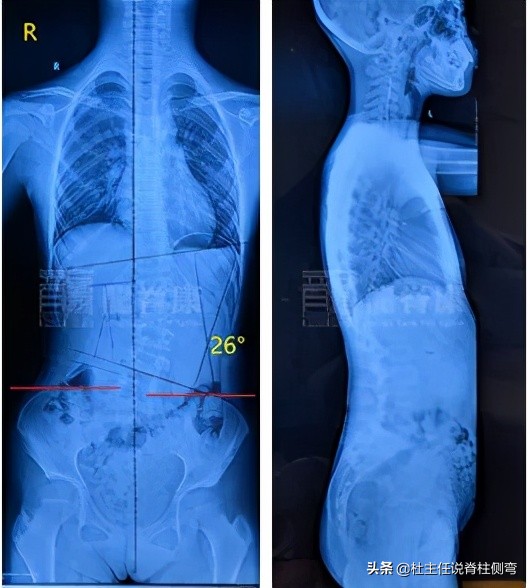

首先为患儿进行了体表检查发现:左腰隆起,ATR:9°,臀右移。结合外院全脊柱X光检查示:以L2为中心向左侧凸,Cobb角≈26°,Risser征:0级,危险系数3.25,脊柱纵轴向左侧偏移,颈椎生理曲度变直,胸腰椎生理曲度可。外院双下肢全长片检查示:右下肢股骨较左侧长。

全脊柱X光检查

因此诊断患儿是青少年特发性脊柱侧弯伴真性长短腿 。我的诊断依据是:根据患儿的全脊柱X光测量出Cobb角约为26°,而且左侧腰部肌肉隆起ATR约9°,无其他特殊病史及体表检查,可排除是由其他疾病引起的,故诊断为青少年特发性脊柱侧弯。另外,从双下肢全长片可见,患儿右下肢股骨明显较左侧长,是真性的长短脚。